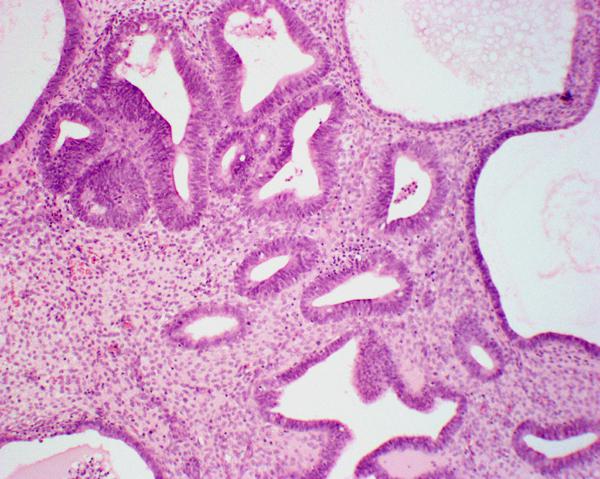

Нередко на эндометрии можно наблюдать новообразования, которые имеют вид узелка (на ножке). Это полипоз эндометрия матки. Размер образований может быть до нескольких сантиметров. Выделяют несколько их видов. В тканях желез диагностируют железистые полипы. Фиброзные могут образовываться в соединительных клетках. Также могут соединяться оба типа – это так называемые железисто-фиброзные полипы. Существует еще одна группа новообразований – аденоматозные. В этом случае в структуре присутствуют атипичные клетки. Специалисты иногда называют такое заболевание предраковым состоянием. Чаще всего полипоз эндометрия диагностируется у женщин после 35 лет. Однако сегодня можно встретить даное заболевание и у подростков, и у молодых женщин. Иногда пациентки даже не подозревают о наличии у себя полипов.

При обычном осмотре у доктора полип обнаружить не удается (разве что его размеры настолько велики, что выходят за полость матки). Обычно полипоз эндометрия диагностируется при проведении ультразвукового исследования. При этом обнаруживается локализация новообразования, его размеры, а также оценивается состояние окружающих тканей. Бывают случаи, когда полип виден не четко. В таких ситуациях необходима гистероскопия. Суть данного метода заключается во введении в матку камеры и специального прибора. При таком исследовании врачу видна вся полость органа. Гистероскопия дает возможность отобрать кусочек эндометрия для дальнейших анализов, а также удалять полипы. Для подтверждения диагноза необходимо проведение гистологических исследований.